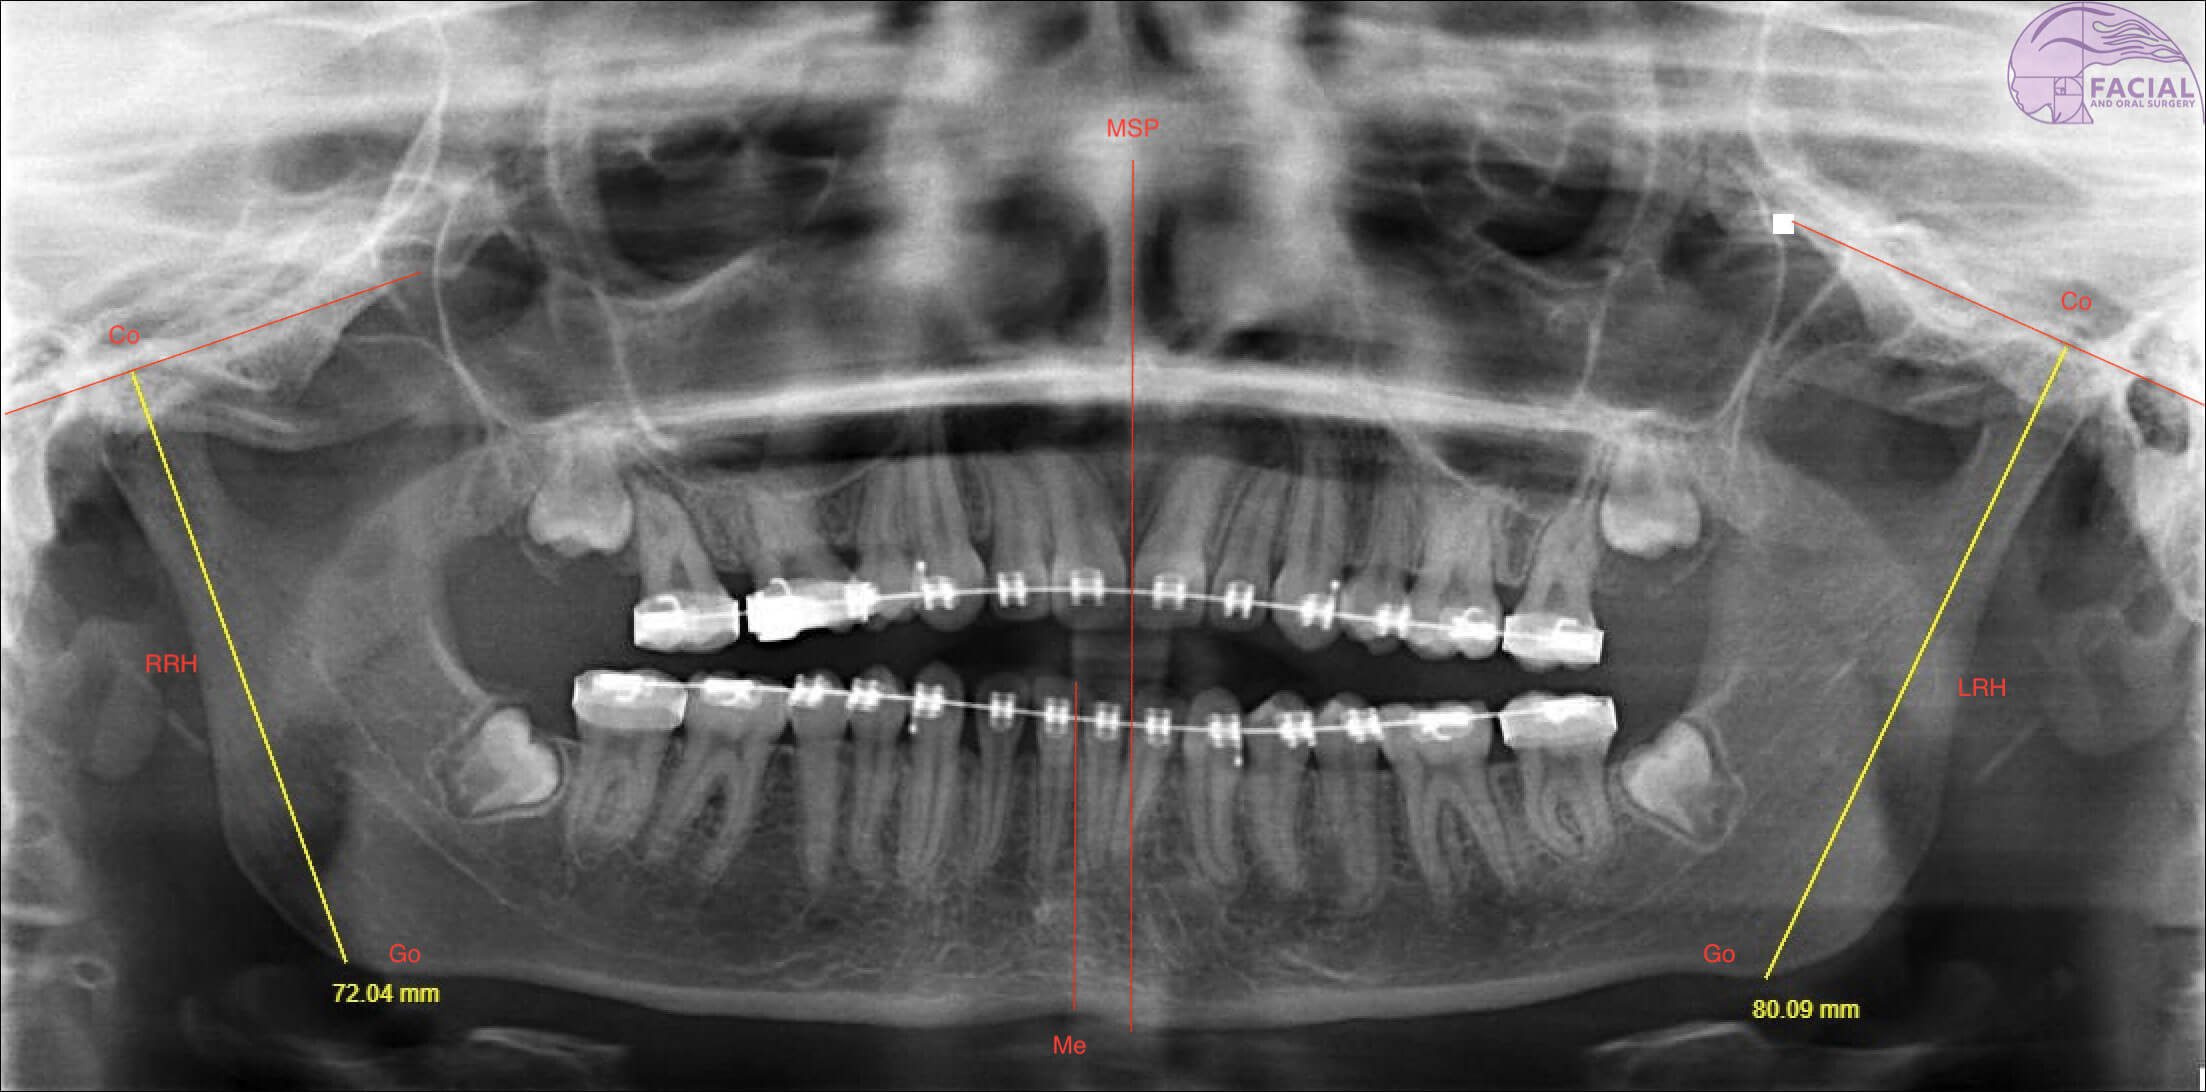

Figure 2a: Case 1 Orthopantomagram: Yaw dominant mandibular asymmetry with chin midline deviation to right.

Right ramus height (RRH). Left ramus height (LRH).

Positive asymmetry index (AI) values indicate that the right mandibular ramus is longer; a negative AI indicate an elongated left side. The AI [14] to evaluate the severity of asymmetry between heights of both sides of the ramus of the mandible:

AI, % = RRH - LRH / RRH + LRH × 100%

- Diagnosis: Skeletal base III growth discrepancy, due to maxillary hypoplasia complicated by left hemi-mandibular elongation causing mandibular asymmetry to the right. Yaw dominant mandibular asymmetry (see Figure 1, 2a and 3).